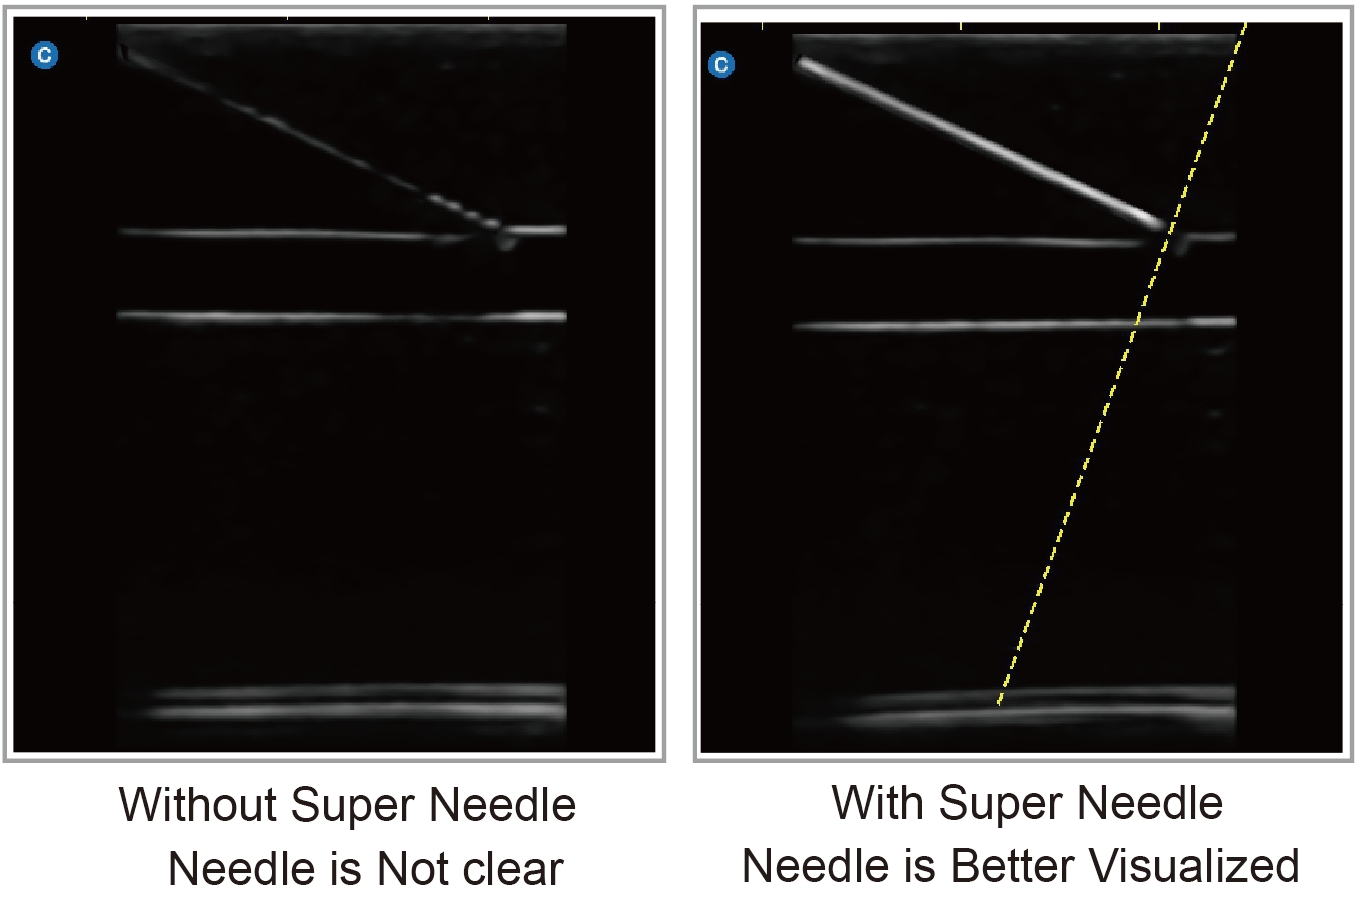

Super Needle(Option)

Super Needle(Option) is our needle enhancement technology supporting angle adjustment up to +/- 20 degrees. It enhances the needle's appearance for a more confident approach to anatomical targets.